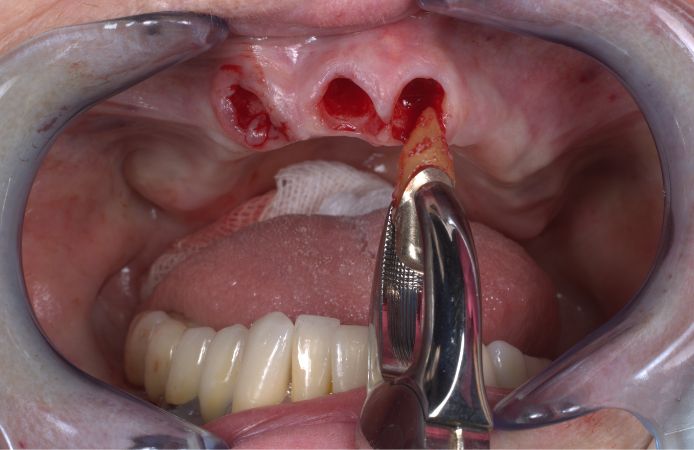

Extraction of failing teeth in anterior maxilla.

Figure 4.

Occlusal view after extraction. A full thickness flap was raised from molar area to molar area and the bone crest was levelled.